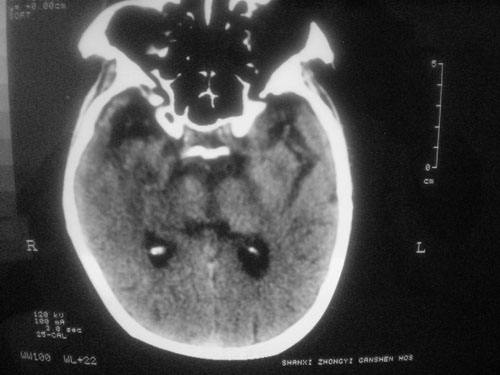

腦供血不足的癥狀會怎樣損害我們的CPU

腦供血不足的癥狀CT圖